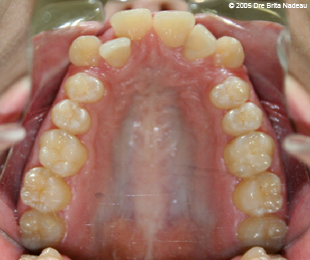

Marie-Hélène Cyr - Upper occlusal view - Before orthodontic treatments and orthognathic surgeries (November 24, 2005)

November 24, 2005 - The constriction of my maxilla and the crowding of my teeth are visible here.